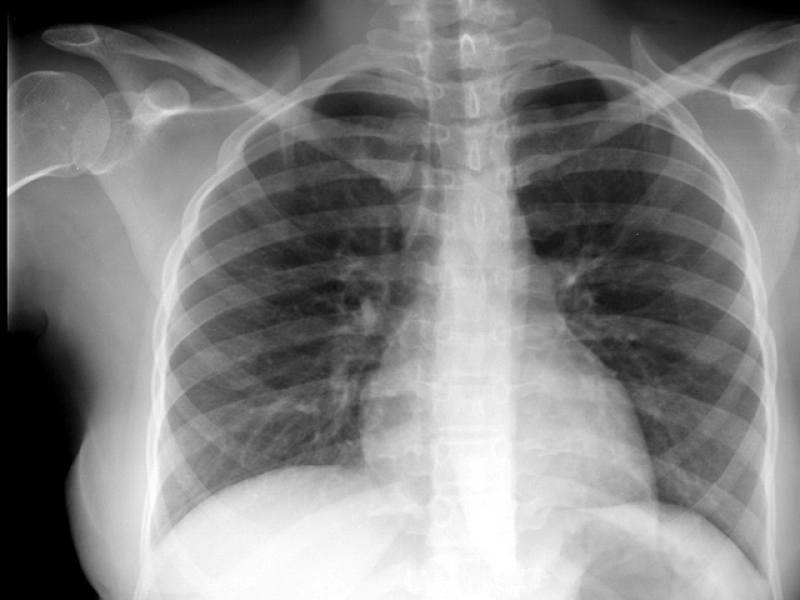

Impressora para Raio-x

RS IMPRESSORASUma impressora para raio-x deve ser específica para que haja o perfeito resultado, principalmente, se houver algum incoveniente que necessita de tratamento. Esse tipo de equipamento é...

Uma impressora para raio-x deve ser específica para que haja o perfeito resultado, principalmente, se houver algum incoveniente que necessita de tratamento. Esse tipo de equipamento é imprescindível em hospitais e clínicas.

Para uma peça de excelência, é de extrema autoridade contar com a ajuda de profissionais especializados e aptos a expandir um serviço de particularidade.

Uma impressora para raio-x deve ser específica para que haja o perfeito resultado, principalmente, se houver algum obstáculo que necessita de tratamento. Esse tipo de equipamento é imprescindível em hospitais e clínicas.

Para uma peça de excelência, é de extrema seriedade contar com a ajuda de profissionais especializados e aptos a ampliar um serviço de particularidade.

Impressora para Raio-x

Impressora para Raio-x

Impressora para Raio-x

RS IMPRESSORASUma impressora para raio-x deve ser específica para que haja o perfeito resultado, principalmente, se houver algum obstáculo que necessita de... Cotar Agora Saiba Mais

Impressora para Raio-x

Impressora para Raio-x

Impressora para Raio-x

RS IMPRESSORASUma impressora para raio-x deve ser específica para que haja o perfeito resultado, principalmente, se houver algum incoveniente que necessita de... Cotar Agora Saiba Mais